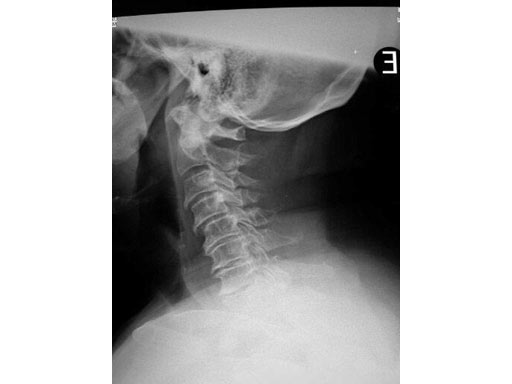

63 -year- old female with multilevel cervical myelopathy and stenosis.